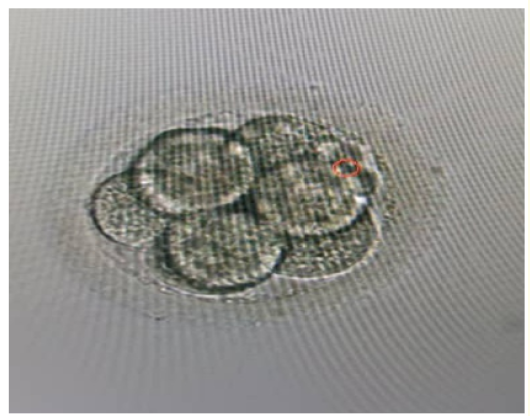

Misdiagnosis of Intra-Uterine Fistula as Hydrosalpinx Post Embolization for a Uterine Myoma: What Went Wrong?

Teddy Tadros, Laura Melado, Jonalyn Edades, Barbara Lawrenz, Francesco Ruiz and Human Fatemi. 12(6): 01-04.